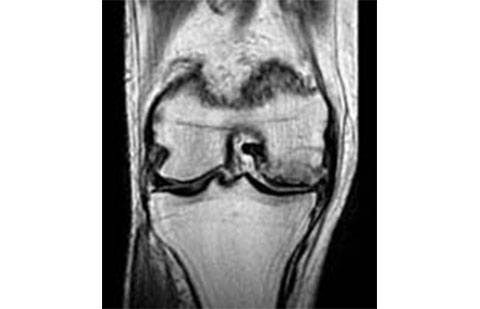

Os exames de imagem são de grande valia para o diagnóstico da fratura por fadiga ou síndrome da insuficiência do joelho. A ressonância é o exame que mais auxilia neste diagnóstico.